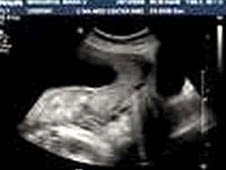

E.胆囊结石并胆息肉,肝转移性癌

24、问答题 肾上腺皮质腺瘤的声像图表现有哪些?